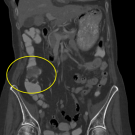

The authors report a case of Streptococcus sanguinis bacteremia that led to the discovery of invasive colorectal adenocarcinoma.

05/18/2020